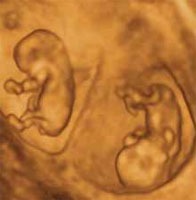

УЗИ-фотографии на сроке 12 недель: